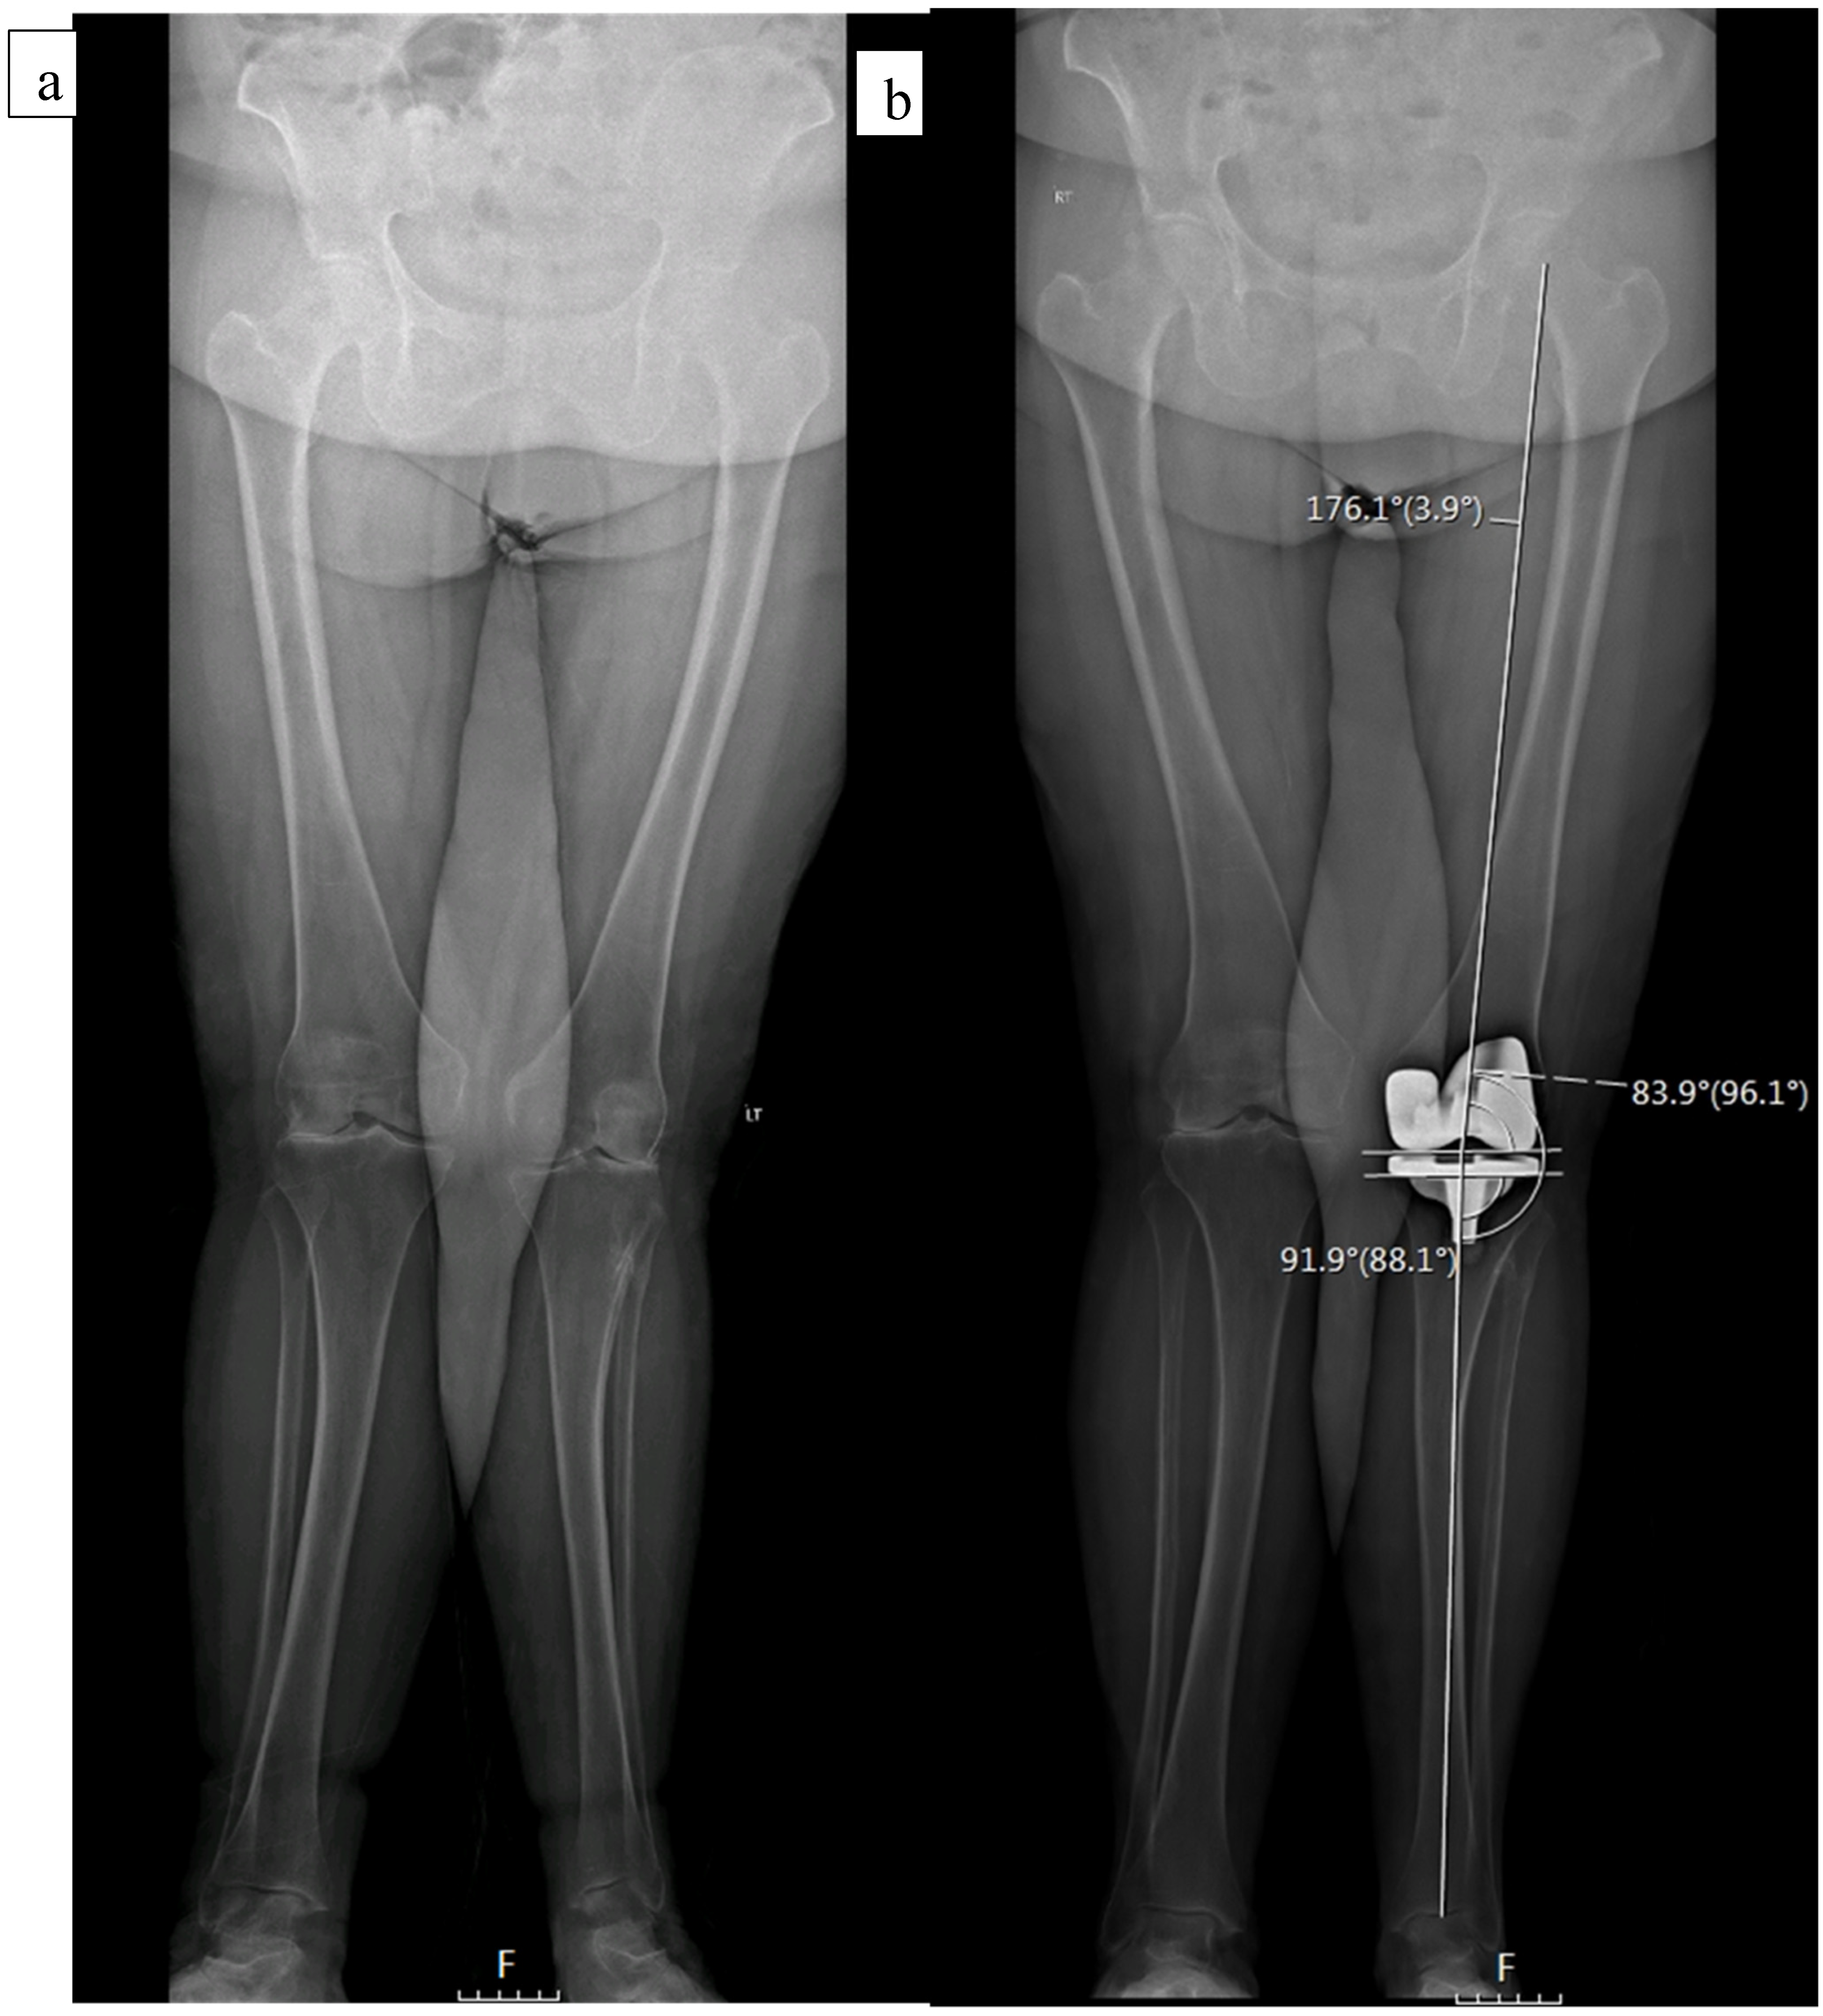

The standard protocol at our institution includes EOS imaging at preadmission testing (2–3 weeks prior to surgery), as well as at the first postoperative follow-up visit, two weeks following discharge (Figure 1). Cases in which a preoperative EOS was not available were excluded. Several measurements were performed, including the medial proximal tibia angle (MPTA), lateral distal femoral angle (LDFA), hip knee ankle angle (HKA), and tibial slope. Radiographic analysis was performed by 3 orthopedic residents who were blinded to the clinical outcome assessment. To confirm inter-observer reliability, 20 overlapping cases were examined showing correlation (kappa) of 0.88 (95% confidence interval 0.79 to 0.96).

Figure 1.

A 76-year-old female with a preoperative valgus alignment (a). Postoperative radiographic analysis shows a MPTA of 88.1°, LDFA of 83.9°, and HKA of 3.9° (b).